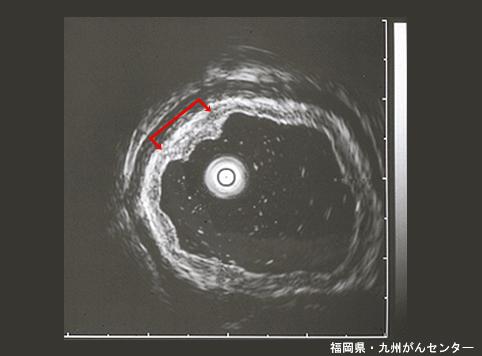

症例提示(所在地,施設名等): 福岡県・ 九州がんセンター

疾患(病理主体)の分類良性上皮性腫瘍/腺腫

部位(臓器別)胃(部位)/前庭

検査方法エコー

腫瘍の肉眼分類0型(表在型)/IIc型(IIc)

病変の最大径(ミリ)10〜14